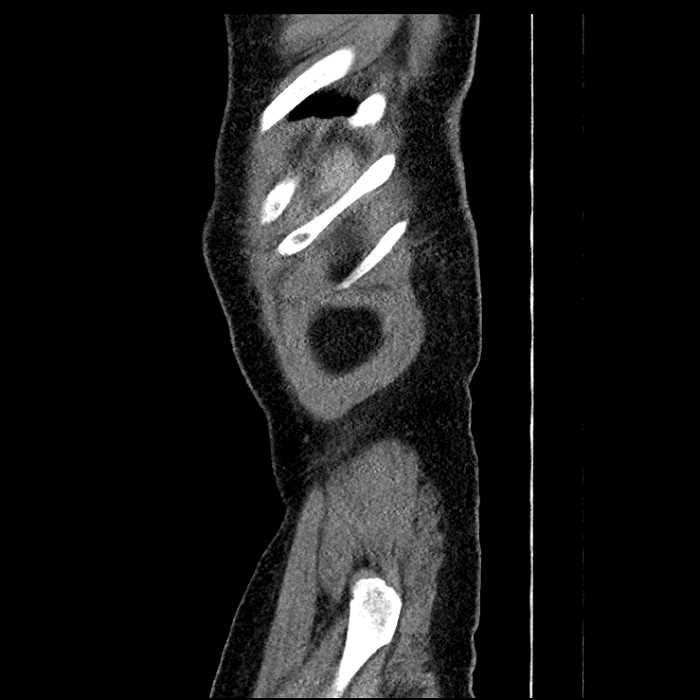

• Large fluid density structure in hepatic segments 7 and 8 measuring 10 x 7 x 7 cm with internal septation and circumferential ill-defined low density compatible with edema

• Peripherally enhancing subcapsular collections along the anterior margin of the left hepatic lobe measuring 3 x 1 cm and 2 x 1 cm

• Mild mural thickening of a segment of the sigmoid colon with adjacent fat stranding and a 1.5 cm fluid and gas collection along the tip of an inflamed diverticulum

• Loss of the normal fat plane between this collection and adjacent loops of small bowel, which demonstrate mural thickening

Acute sigmoid diverticulitis complicated by a small contained perforation and a large abscess in the right hepatic lobe. Additional small subcapsular abscesses along the anterior margin of the left hepatic lobe.

Additionally, loss of the normal fat plane between the peridiverticular collection and adjacent thickened loops of small bowel raises the potential for an enterocolonic fistula.

• The classic CT imaging appearance is a double target sign with internal low density surrounded by an internal enhancing rim (capsule) and a low density external rim (edema)

Hepatic abscess showing the double target sign with low density internally surrounded by a thin inner enhancing rim (red arrow) and ill-defined outer low density rim (yellow arrow). Blue arrow indicates an internal septation. Red arrows: additional smaller subcapsular abscesses. Red arrow: focal contained perforation associated with diverticulitis.